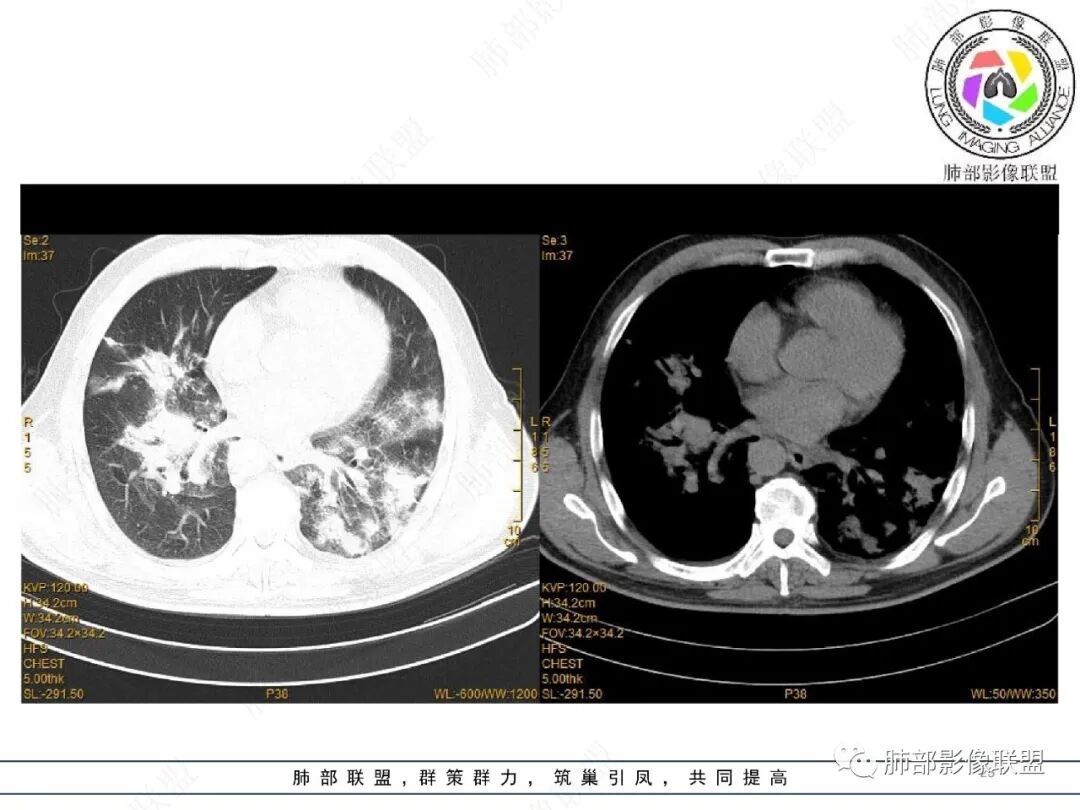

2022.2.17CT显示两肺中内带多发结节影、斑片影、条索影,部分病灶侧向融合与胸膜平行。部分病灶沿着支气管血管束分布、其内支气管稍扩张。部分病灶呈反晕征。大部分病灶边界显示清晰,部分病灶周围可见边界不清的GGO。2022.4.12CT显示两肺中内带多发结节影、条索状、条带状高密度影,边界收缩平直凹陷,大部分病灶沿着支气管血管束分布,亦有位于胸膜下侧向融合与胸膜平行的病灶。总体与第一次CT对比两肺病灶明显吸收。

3、病例小结:

老年男性,两肺多发病灶,整体呈OP样改变,至于是原发性还是继发性的OP,需要临床鉴别。此病例穿刺结果是隐球菌。该病例CT上缺乏隐球菌典型的“在那遥远的胸膜下,多个蘑菇兄弟,可以侧向融合呈长串状与胸膜平行”影像表现,更多是OP样改变,仅凭临床表现或影像资料诊断隐球菌难度比较大。当然也不除外二元论,导致隐球菌的影像表现被掩盖。